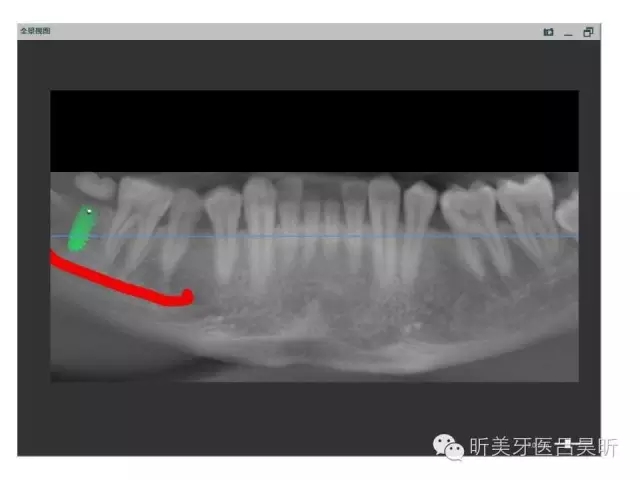

術(shù)前口內(nèi)掃描,設(shè)計(jì)冠修復(fù)方式和種植位點(diǎn)

可見(jiàn)種植位點(diǎn)舌側(cè)區(qū)凹陷,牙槽骨上部舌傾明顯。

擬定種植三維方向

以修復(fù)為導(dǎo)向的種植位點(diǎn)設(shè)計(jì)